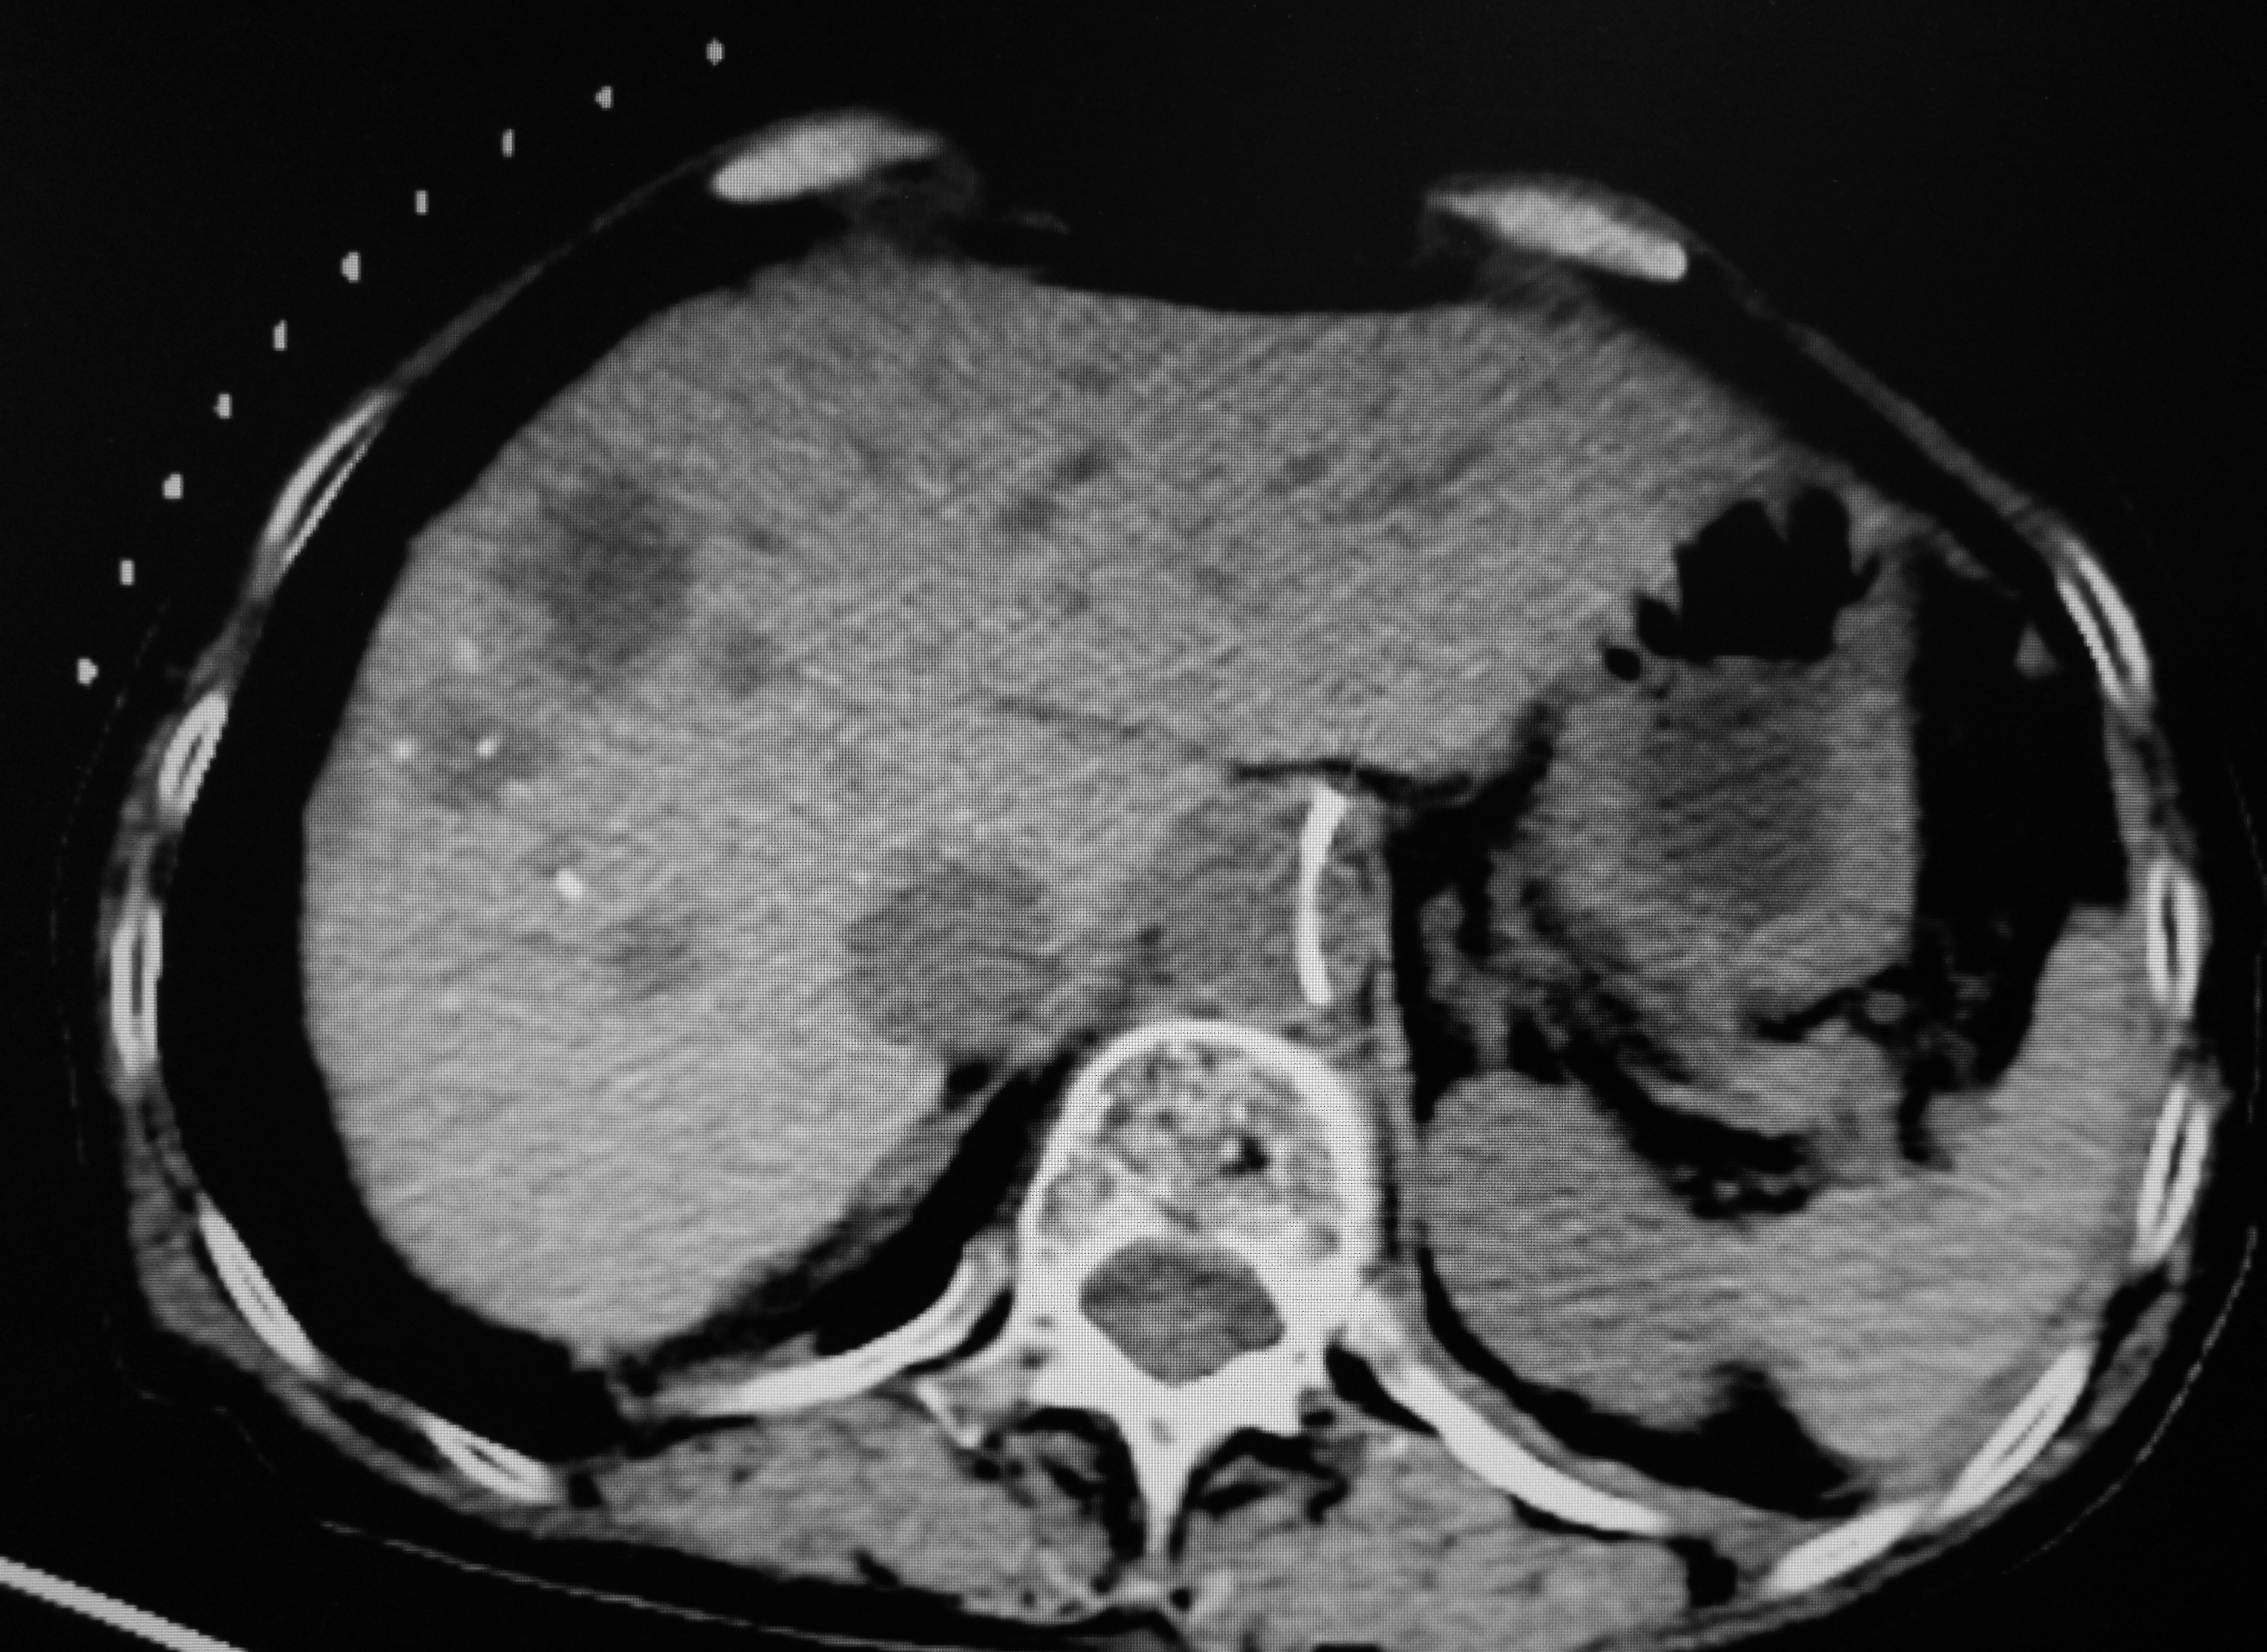

第二步:射频消融前,CT扫描确定进针方向与深度

第三步:CT定位后,消融针穿刺到肿瘤